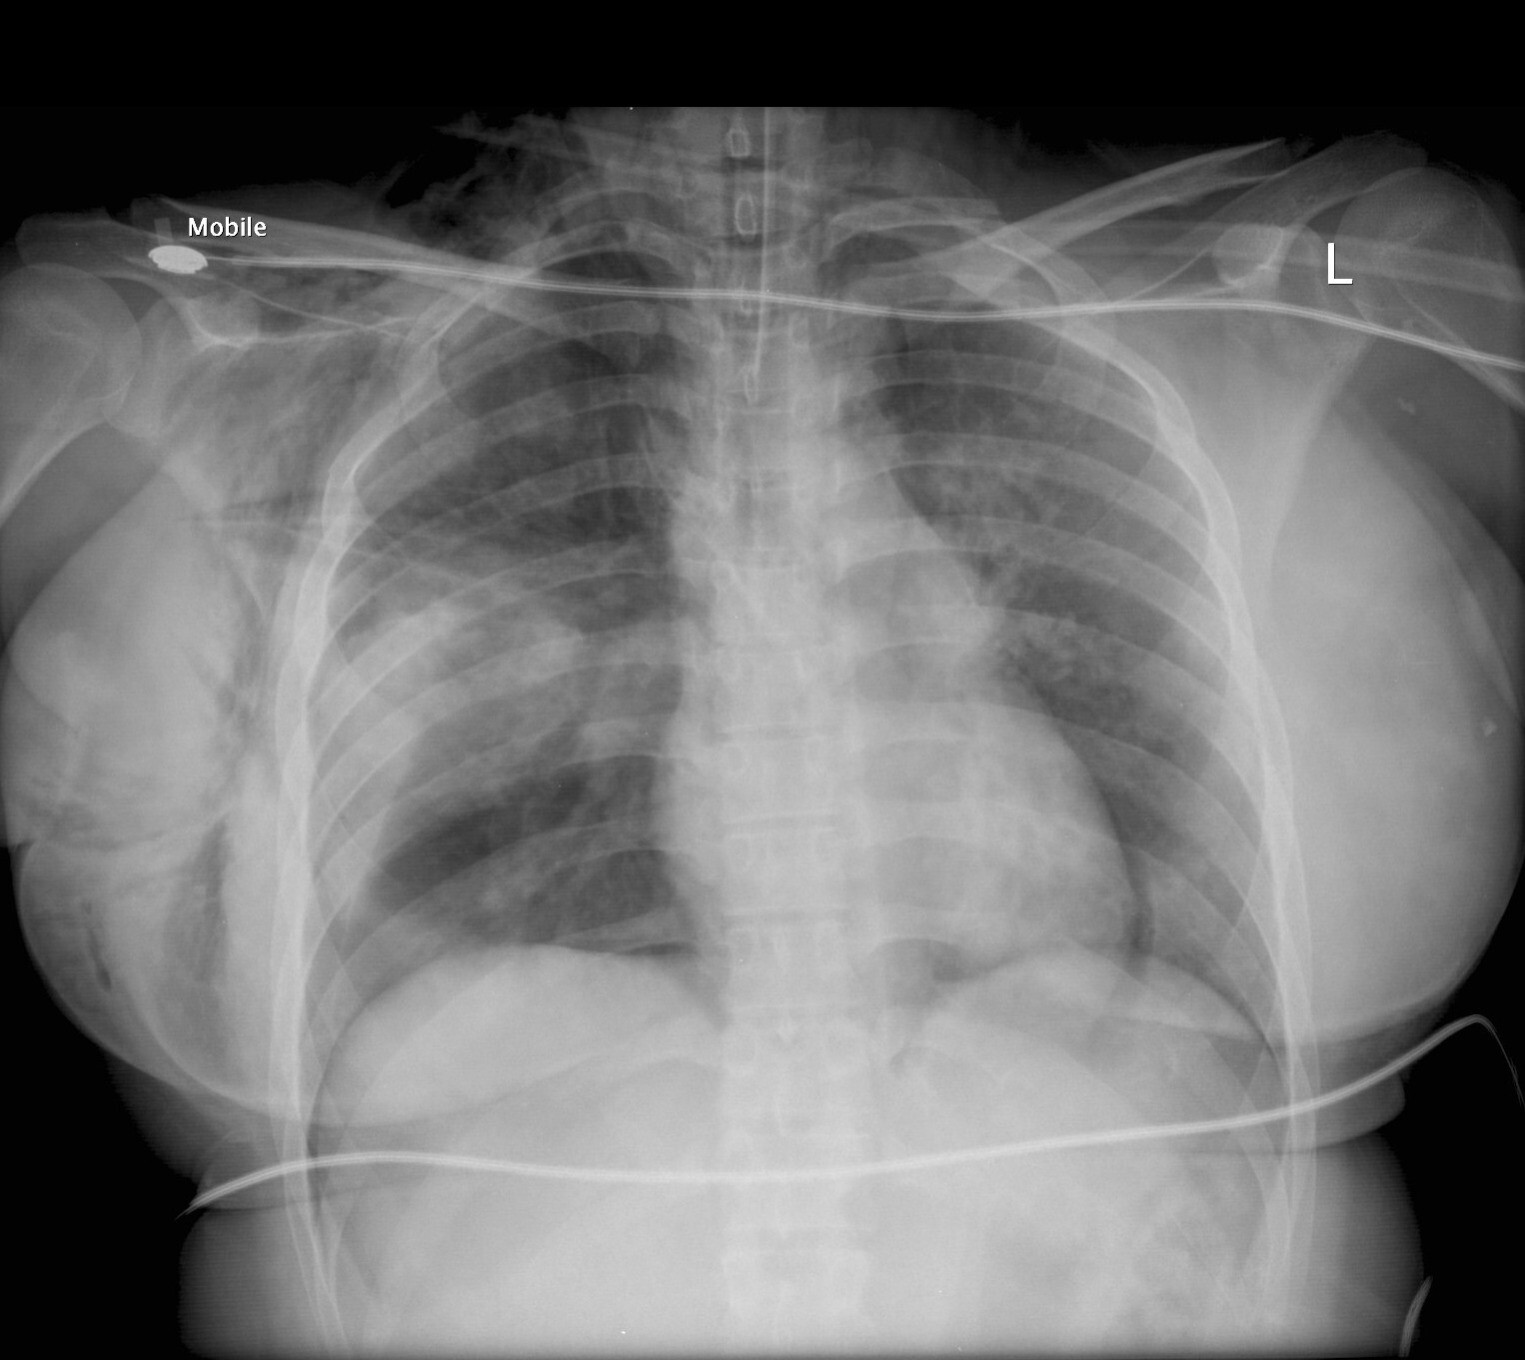

A critically ill 45 year old woman is intubated in the ICU. A procedure is performed and the following test is conducted

What was the procedure?